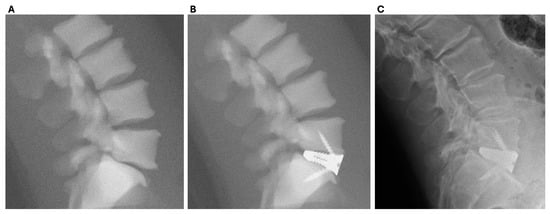

4.4. Efficacy